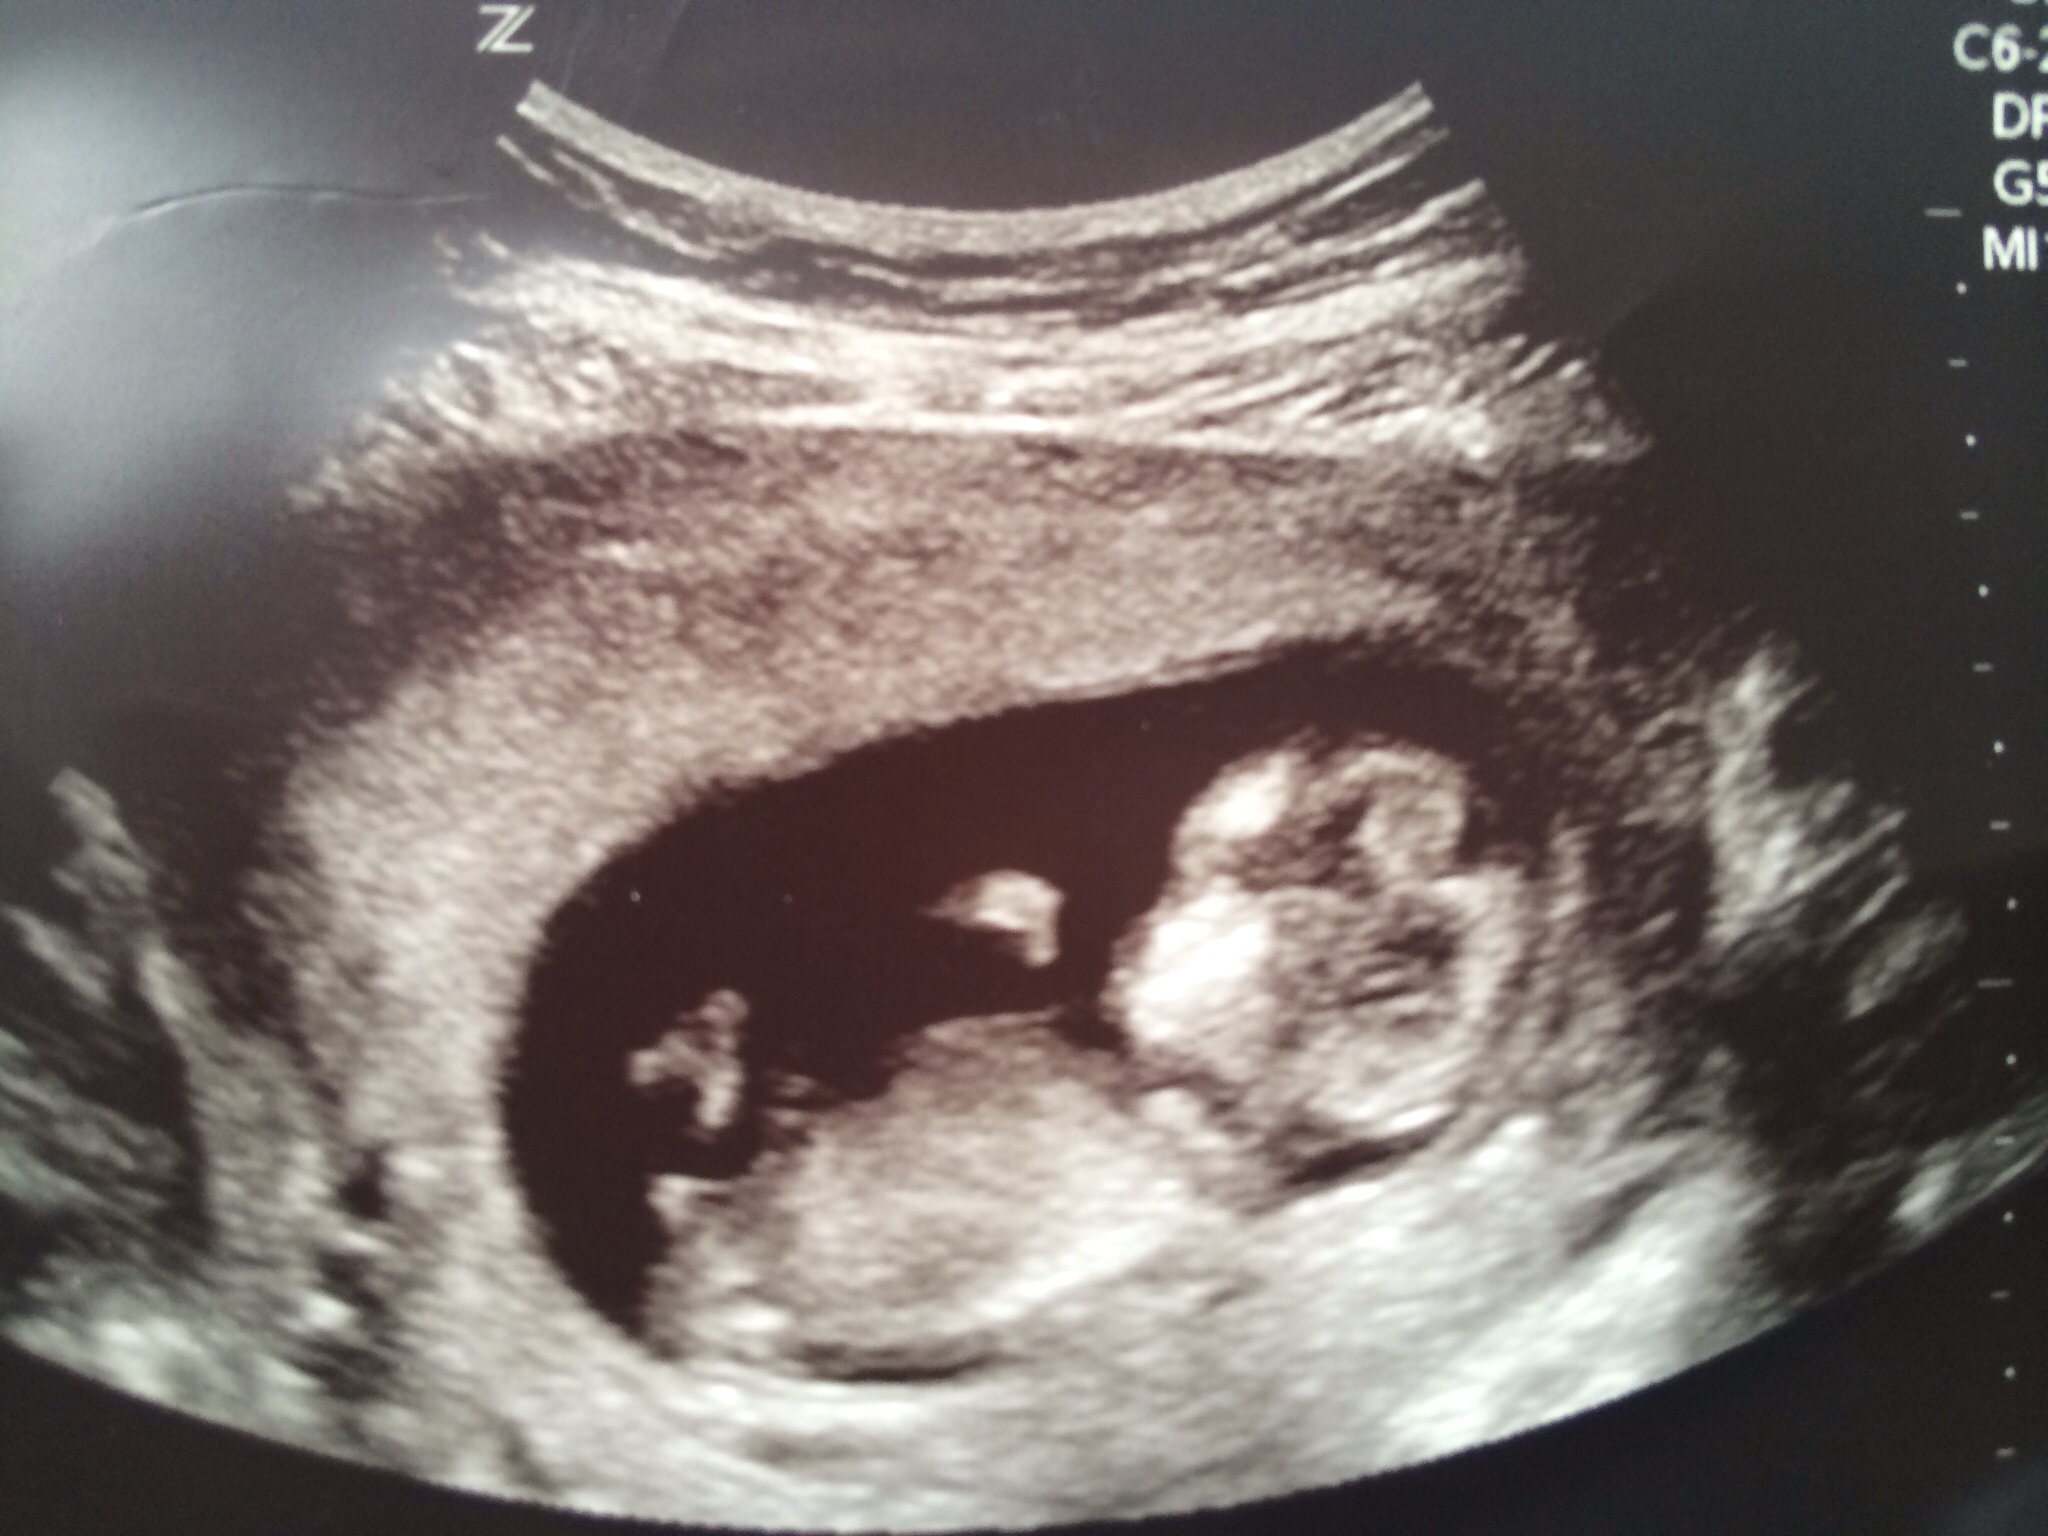

My good day continues! Baby still has a healthy heartbeat "in the 160s" which she was able to just barely pick up on the Doppler. Hopefully that means I'll be able to get it myself soon.